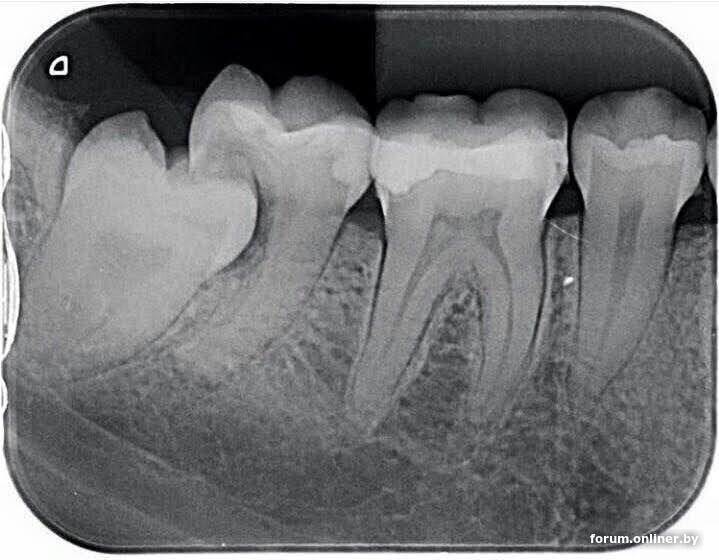

Посоветуйте, пожалуйста, хорошего стоматолога, вот прям золотые руки. Можно просто ФИО, где приём - сама найду. Нужно заменить большую пломбу, которая, в общем-то, составляет бОльшую часть зуба. Обычно лечила в Любимом стоматологе, но что-то сейчас у них вообще стали цены уххх, хотя врач там, к которому я хожу, вот как раз из категории "золотые руки"... Хочу попробовать найти аналог по более адекватной цене.